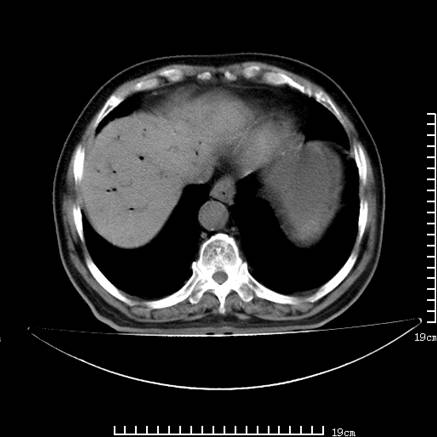

以下是引用lirenxiong在2008-7-19 22:01:00的发言:[br]胆总管结石并胆系感染,胆囊切除术后改变!左肾未见!左肾上腺增生肥大?请全腹扫描,增强!

以下是引用sch2008在2008-7-19 22:03:00的发言:[br]肝内胆管及胆总管积气,并胆总管结石,考虑;胆囊切除术后,胆系感染

以下是引用lirenxiong在2008-7-19 22:01:00的发言:[br]胆总管结石并胆系感染,胆囊切除术后改变!左肾未见!左肾上腺增生肥大?增强!